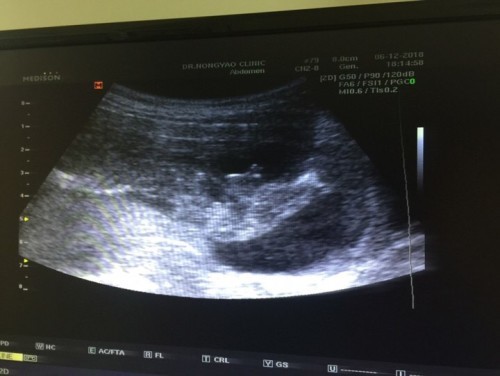

?ตอนนั้นผมได้พาแฟนไปซาวเพศที่คลีนิคช่วง3เดือนครึ่ง หมอบอกว่าได้ลูกชาย80% ตอนนี้อายุครรภ์ได้34สัปดาห์ ไม่ทราบว่า เพศของลูกสามารถเปลี่ยนได้ไหมคับ เพราะตอนที่ไปซาวอายุครรภ์ยังน้อย ?? รูปตอนซาวผมก็ดูเป็น?